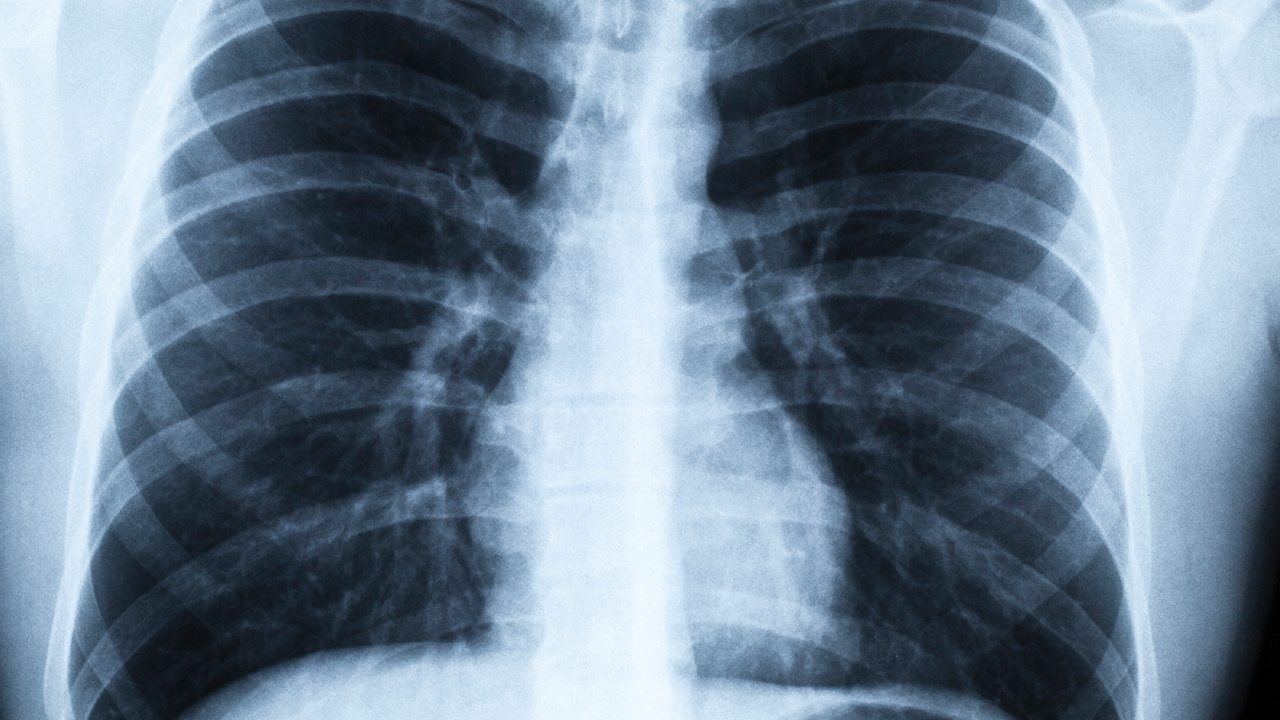

肺炎支原體是社區獲得性肺炎的常見(jiàn)病原體之一,但其陰性結果并不等同于無(wú)肺炎。細菌性肺炎如肺炎鏈球菌感染、金黃色葡萄球菌感染等均可引起類(lèi)似癥狀。病毒性肺炎如流感病毒、呼吸道合胞病毒感染也可能導致肺部炎癥。部分非典型病原體如衣原體、軍團菌等同樣需通過(guò)特異性檢測排除。臨床表現與影像學(xué)檢查對肺炎診斷更為關(guān)鍵,例如胸部X線(xiàn)或CT顯示肺部浸潤影時(shí),即使支原體陰性仍需結合其他檢查綜合判斷。